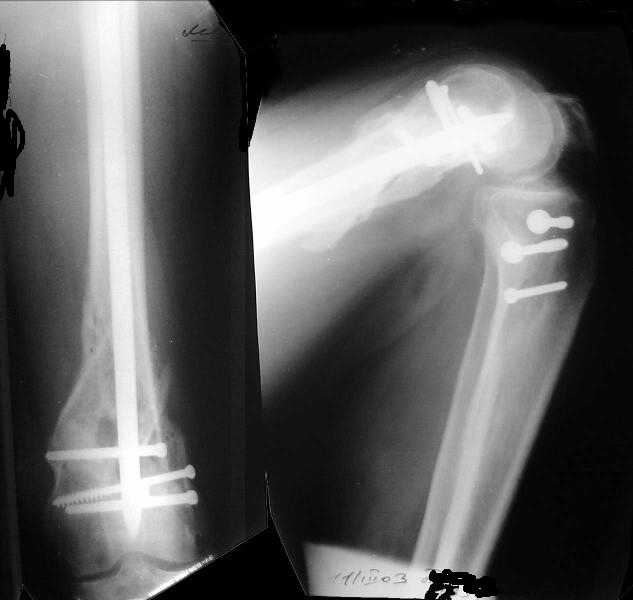

Отправитель: Alexander Chelnokov 27 Декабрь 2003, 21:34

1

Sorry but I've just prepared postop images - attached. A solid 13 mm nail was used. A few degrees of recurvation appears to be which i missed on image intensifier. I'm still uncertain about

advantages/disadvantages of ante/retrograde nailing for such fractures.

Отправитель: V.M.Iyer 27 Декабрь 2003, 21:36

The fixation as you have done is excellent. The locking screws on either side of the # are so apart. When we put in a supracondylar nail thro a keyhole incison in the knee, the locking bolts will be nearer the # and will be more stable allowing him to bear wt early. That was the reason the supracondylar nail was innovated. The locking is done by jig and no freehand method saving time.